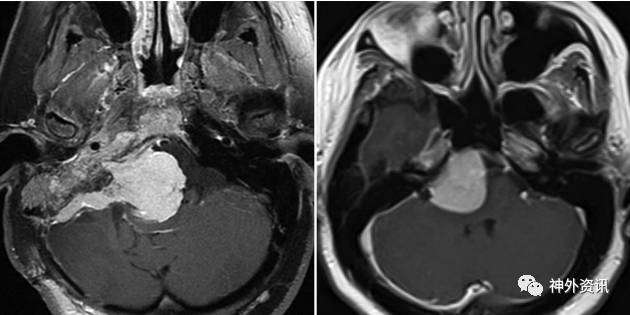

当肿瘤生长偏向岩骨嵴、伴或不伴侵犯内听道(IAC)或海绵窦时,选择乙状窦后入路。远外侧入路适用于肿瘤靠近岩斜区下方、延伸至颈静脉孔或舌下神经管外侧。对于大多数未延伸至内听道、颈静脉孔或舌下神经管外侧的肿瘤,选择内镜下经鼻蝶入路较合适。如果肿瘤涉及广泛,可采用EEA与RSA或FLA联合入路(图1)。

图1. 依据肿瘤的影像学特征选择手术入路。岩斜区脑膜瘤扩展至小脑桥脑角和侵犯内听道时,选择乙状窦后入路(图左);位于岩斜区中部向外上扩展至内听道水平的脑膜瘤,可采用内镜下经鼻蝶入路(图右)。